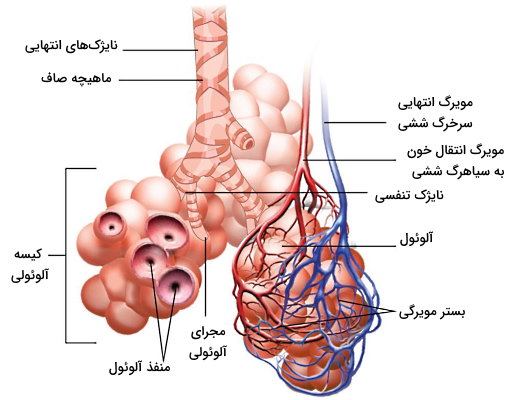

نایژکهای شاخههای انتهایی و بسیار باریک درخت تنفسی هستند. دیواره این مجاری به جای غضروف و سلولهای گابلت ترشحکننده مخاط از فیبرهای ماهیچه صاف و سلولهای کلاب تشکیل شده است. سلولهای کلاب لیپوپروتئینی ترشح میکنند که کشش سطحی دیواره این مجاری را کاهش میدهد و مثل غضروفهای بخشهای قبلی مسیر تنفسی از بسته شدن مجاری جلوگیری میکند. در انتهای بسیاری از نایژک آلوئول وجود دارد که محل تبادل گازهای تنفسی است. نایژکهای انتهایی که آلوئول ندارند در تبادل گازها شرکت نمیکند.

آلوئولها کیسههای بسیار کوچکی هستند که دیواره آنها از یک لایه سلول پوششی سنگفرشی تکلایه تشکیل شده است. دیواره نازک این کیسه امکان انتشار ساده گازها از دیواره مویرگ را فراهم میکند. سورفاکتانت ترشح شده از سلولهای دیواره این کیسه از تغییر شکل کیسه به دلیل تغییر فشار گازهای تنفسی جلوگیری کرده و کشش سطحی دیواره را کاهش میدهد. تعداد زیادی آلوئول در انتهای نایژک وجود دارد که به شکل خوشه انگور کنار هم قرار گرفته و کیسه هوایی یا آلوئولی را تشکیل میدهد. منفذ کوچک دیواره بین دو آلوئول کنار هم ارتباط برقرار میکند.